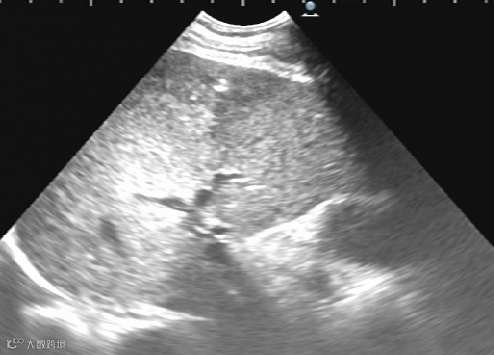

卵巢巧克力囊肿硬化治疗:

治疗前

治疗后